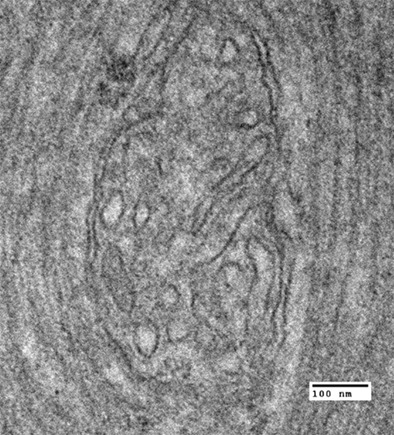

Mitochondrial Developmental encephalopathy with bilateral optic neuropathy related to homozygous variants in IMMT gene

Abstract IMMT gene codes for mitofilin, a mitochondrial inner membrane protein that regulates the morphology of mitochondr...